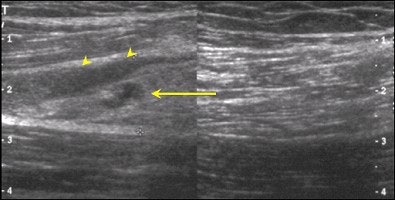

| A sonogram of the same patient examined above reveals a macroscopic tear (arrow) as evidenced by an area of low echogenicity with a degree of muscle retraction. The hypoechoic rim around this tear correlates with the surrounding fluid visualised on MR imaging (arrowheads). |

So far, sonography has proved to be less than ideal for HMC imaging. The low echogenic signal of edema on the background of normal dark gray muscle on sonography is difficult to appreciate. In addition, sonography is disadvantaged by the fact that it is highly operator dependent.

However, the advent of new high-frequency probes, and the advantage of clinical correlation with a cooperative patient, make it possible to provide a more focused and detailed examination. While this raises the sensitivity of sonography, it does not make it the gold standard for hamstring imaging.